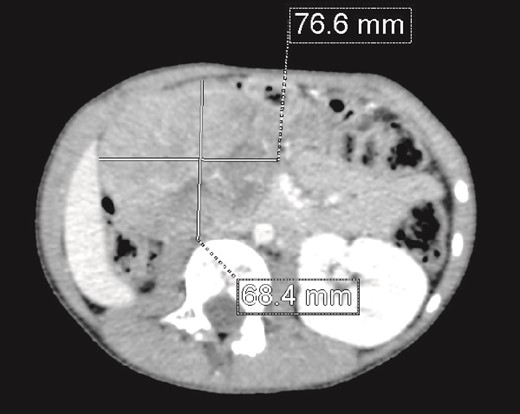

We present the case of an 8-year-old boy with no significant medical history and no prenatal diagnosis of congenital renal malformation. During a physical examination following a minor abdominal injury sustained while playing, a right flank abdominal mass was discovered. Clinically, the patient’s general condition was stable. The mass was non-tender, firm, and fixed to deep planes while mobile over superficial planes. There was no evidence of varicocele. Abdominal ultrasonography and computed tomography (CT) revealed a well-circumscribed, well-encapsulated solid mass measuring 9 × 6 cm, with areas of necrosis. The mass was located in the right kidney, in contact with the cephalic portion of the pancreas and closely abutting the inferior vena cava, which was displaced to the left. The right kidney was not visualized, and no secondary lesions were detected (Fig. 1). Magnetic resonance imaging (MRI) was performed to further characterize the tumor’s origin. However, it confirmed only the presence of the tumor and the absence of normal renal parenchyma, providing no additional information regarding the origin of the upper right abdominal quadrant mass (Fig. 2). Given the unclear origin of the tumor, a CT-guided biopsy was performed. Pathological analysis of the biopsy revealed nephroblastoma without signs of anaplasia. The patient was subsequently treated with neoadjuvant chemotherapy, consisting of vincristine and actinomycin D for 4 weeks, following the SIOP 2001 protocol, and was scheduled for nephrectomy. Post-chemotherapy CT evaluation demonstrated a 75% reduction in the size of the right kidney mass (Fig. 3). The patient underwent an open nephrectomy. Intraoperatively, an atretic ureter was identified, with no visible normal renal parenchyma. An extended right nephrectomy was performed (Fig. 4a and b).

CT scan: A solid mass of 9 × 6 cm of diameter containing some areas of necrosis, well circumscribed, well encapsulated at the expense of the right kidney in contact with the cephalic portion of the pancreas and in close contact with the inferior vena cava, which is pushed to the left. The right kidney is not visualized.

CT scan evaluation after chemotherapy: Regression in size of the right kidney mass with an estimated response of 75%.